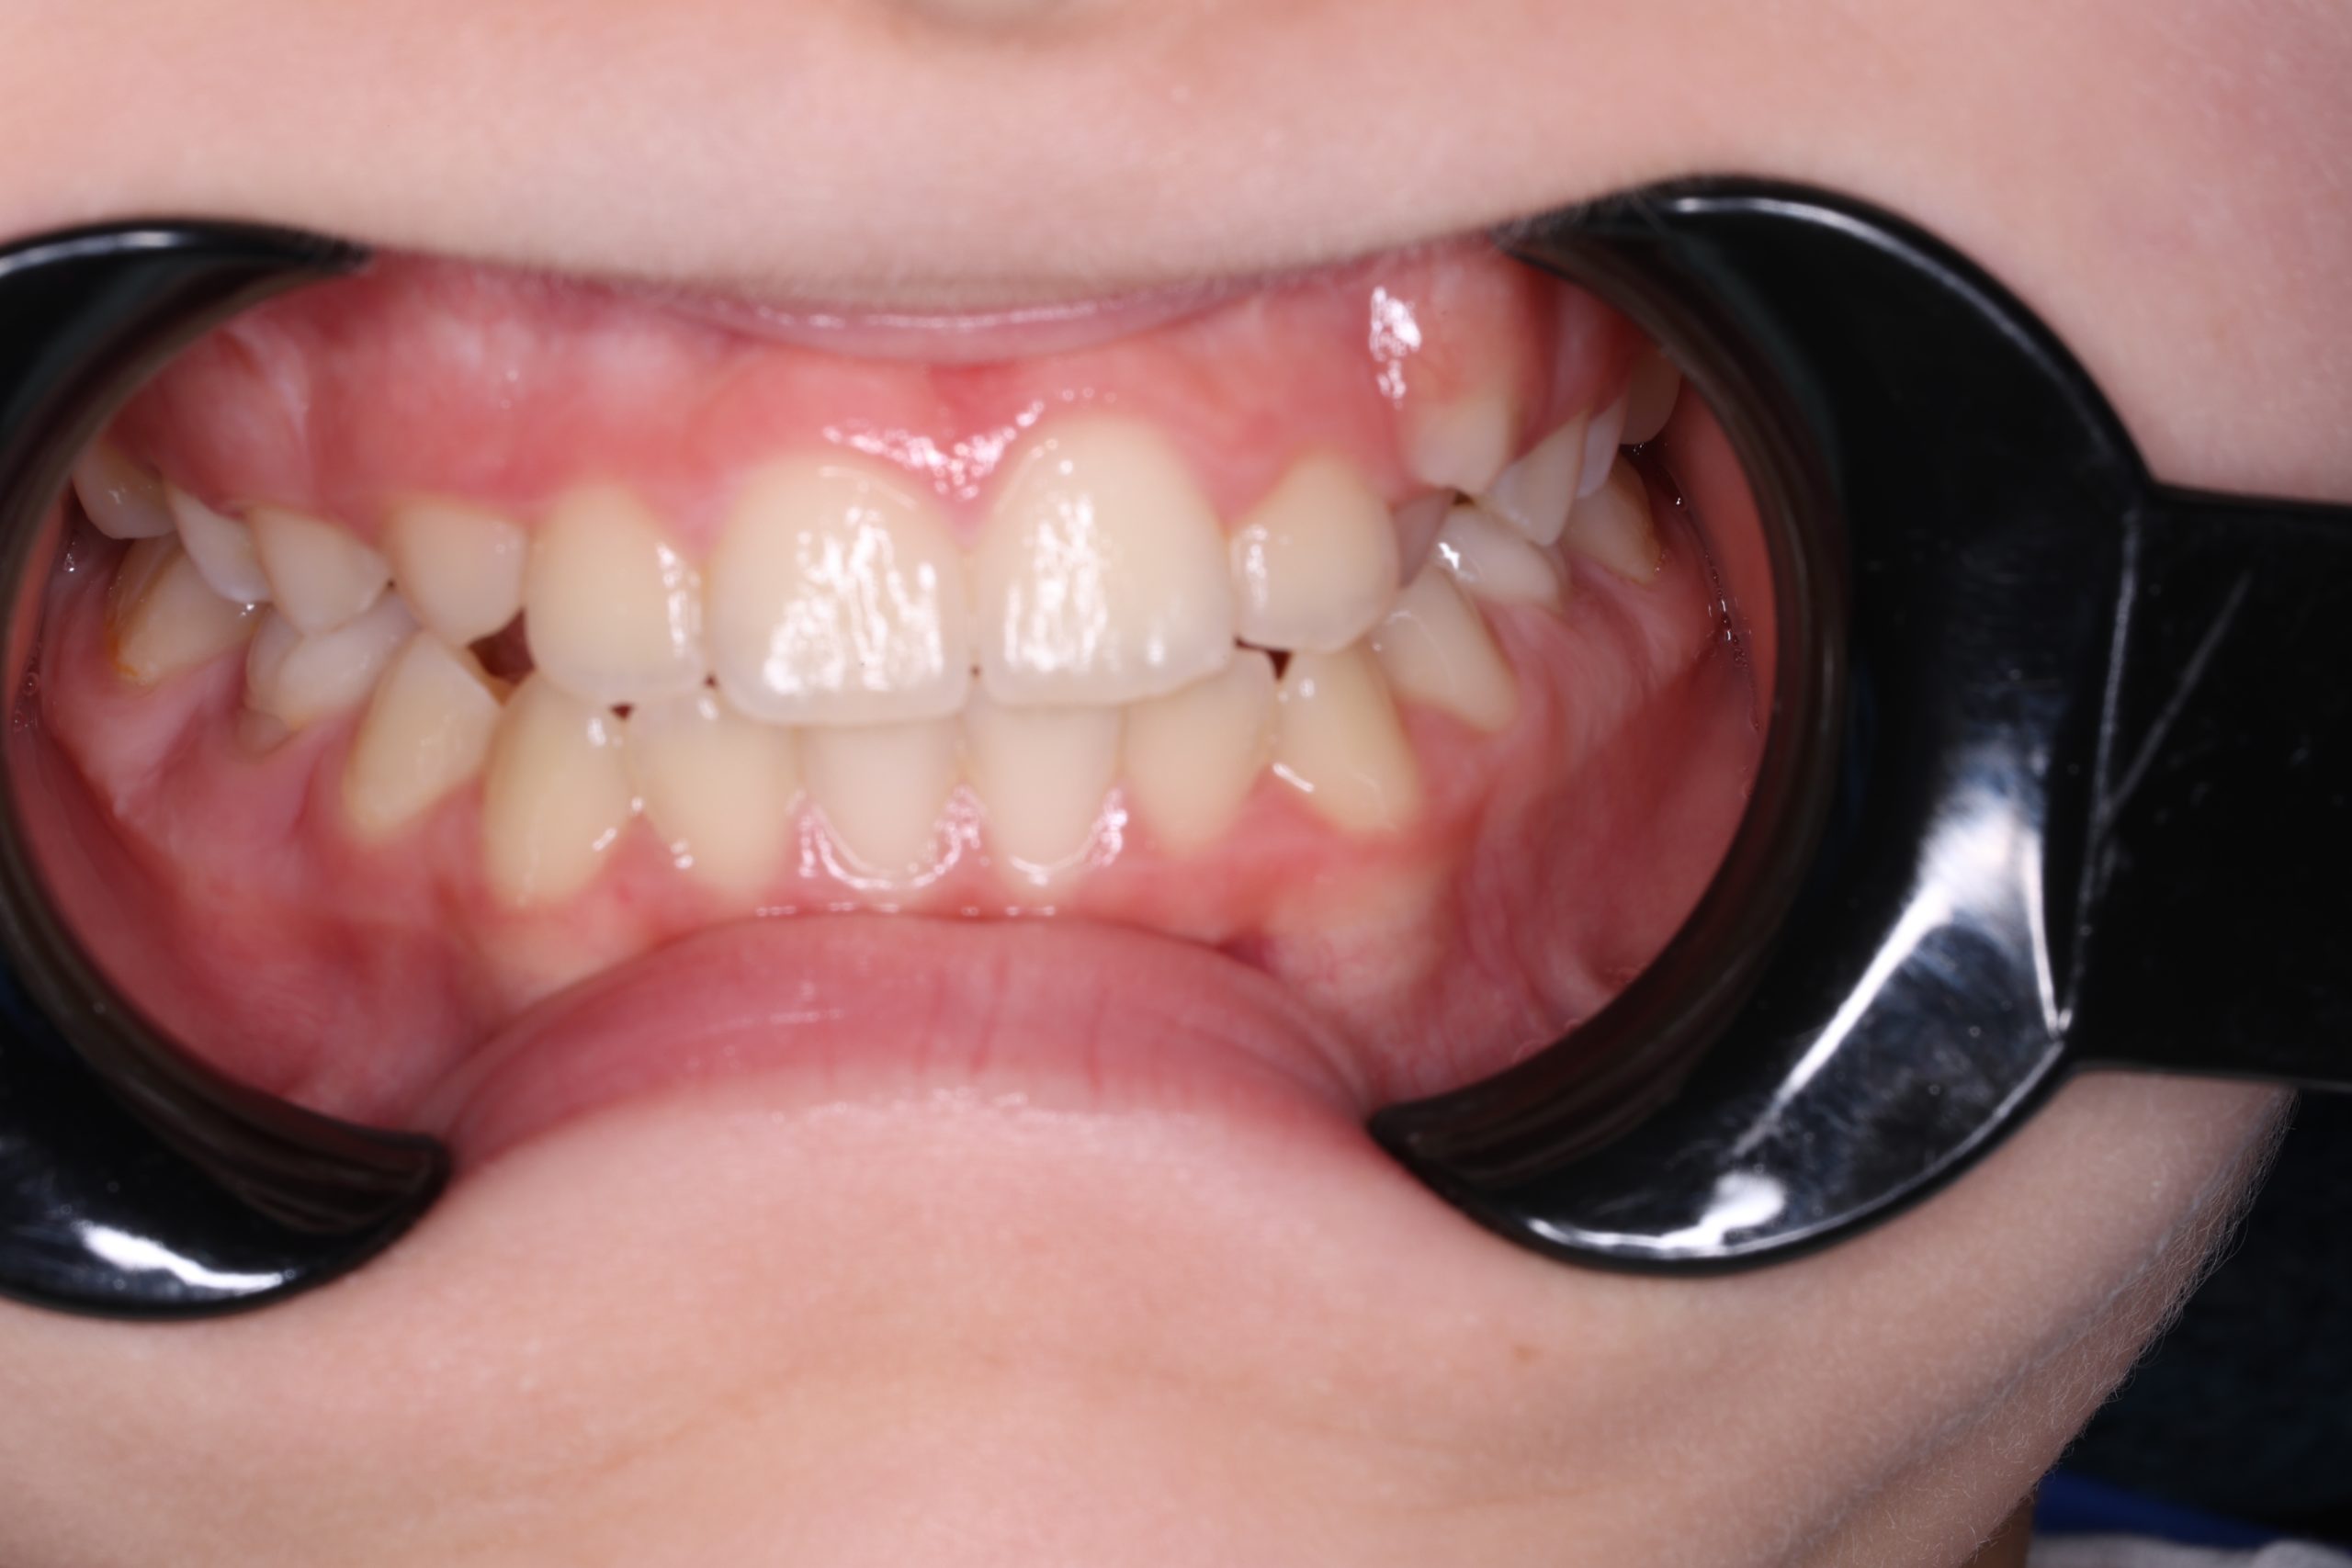

- Detailed Examination

We examine the condition of teeth, gums, and bite. - Plaque Disclosure with Special Indicators

Areas that weren’t cleaned well appear purple. The darker the shade, the older the plaque. This helps both kids and parents understand where brushing needs to improve. - Brushing Training & Home Care Tools Selection